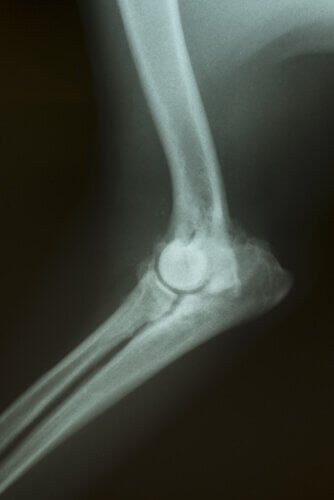

In base ai sintomi, potrebbero essere necessari alcuni esami per determinare la causa del problema. Potranno essere fatti: analisi del sangue, radiografie, ultrasuoni, tomografie, ecc.